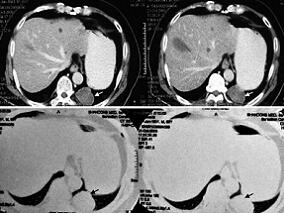

1小时条评论以下列举四类笔者收治的罕见腹膜后肿瘤个案,希望以点代面,经验交流和总结。 (一)罕见的腹膜后促纤维增生性小圆细胞瘤个案 患儿:女,5岁。因阵发性腹痛3个月,加重2天,发现腹部包块1天入院。3个月前出现无明显诱因腹痛,当地对症治疗后缓解,未进一步检查。此...